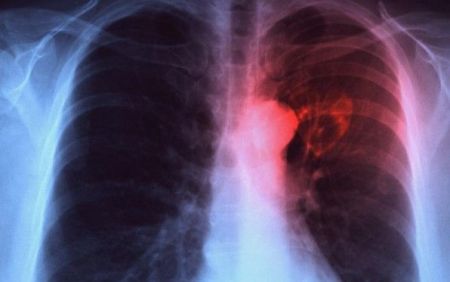

Αμερικανοί εππιστήμονες εκπαίδευσαν ένα σύστημα τεχνητής νοημοσύνης να μελετά ακτινογραφίες και να κάνει διαγνώσεις φυματίωσης. Το σύστημα αναμένεται να βοηθήσει μελλοντικά γιατρούς απομονωμένων περιοχών και αναπτυσσόμενων χωρών, που δεν έχουν πρόσβαση σε εξειδικευμένους ακτινολόγους.